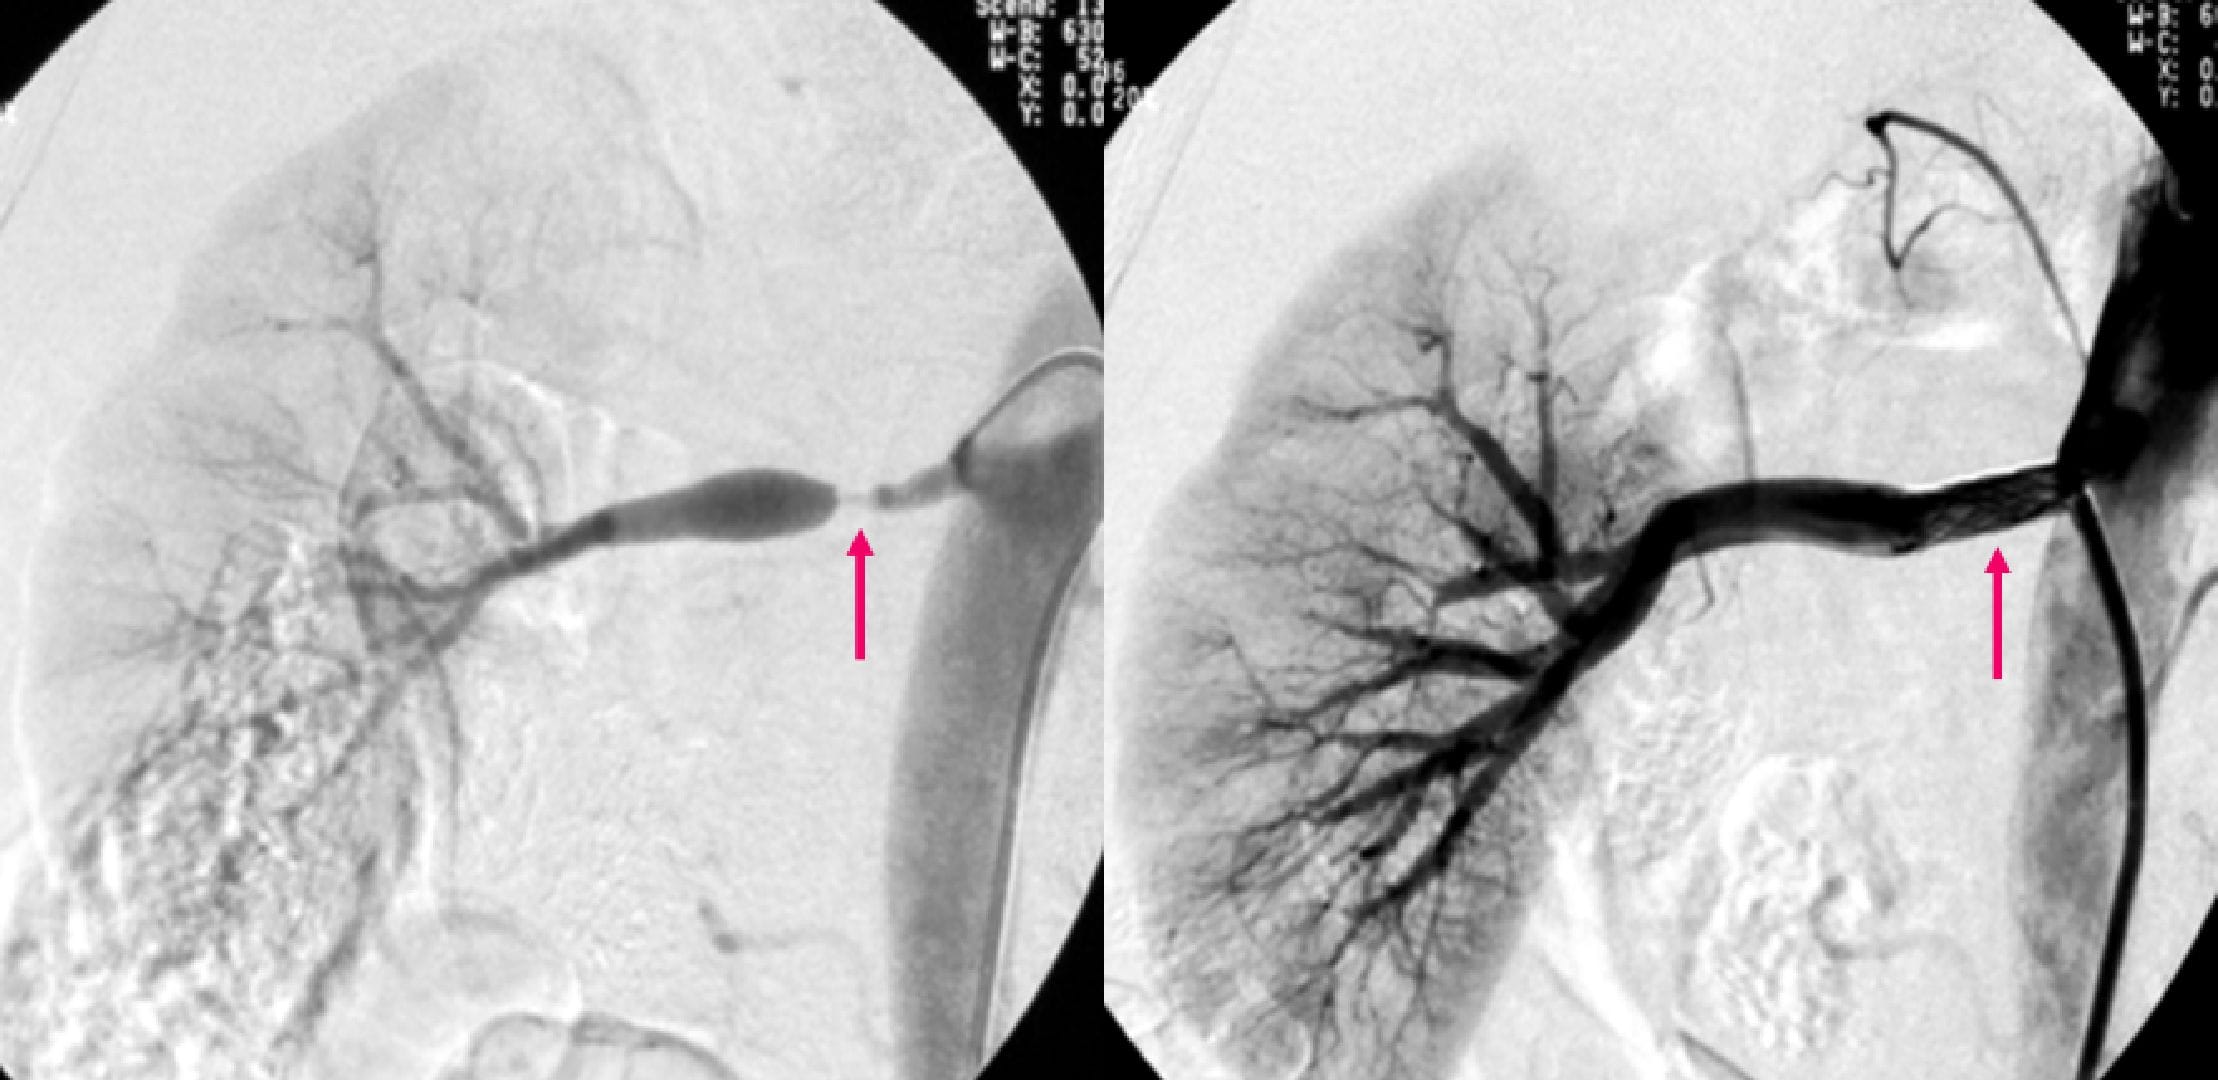

【消化管出血塞栓症例】

(左図・中図)小腸出血の患者さんです。腸管を栄養する血管にカテーテルを挿入し、血管造影を行いました。空腸に造影剤の血管外漏出像が認められます(矢印)。

(右図)金属コイルによる塞栓を行い、止血に成功しました(矢印)。

【術後出血ステントグラフト留置症例】

(左図)上腸間膜動脈本幹より血管外漏出像(出血)が認められます(矢印)。

(右図)ステントグラフトを留置して(矢印)、止血に成功しました。